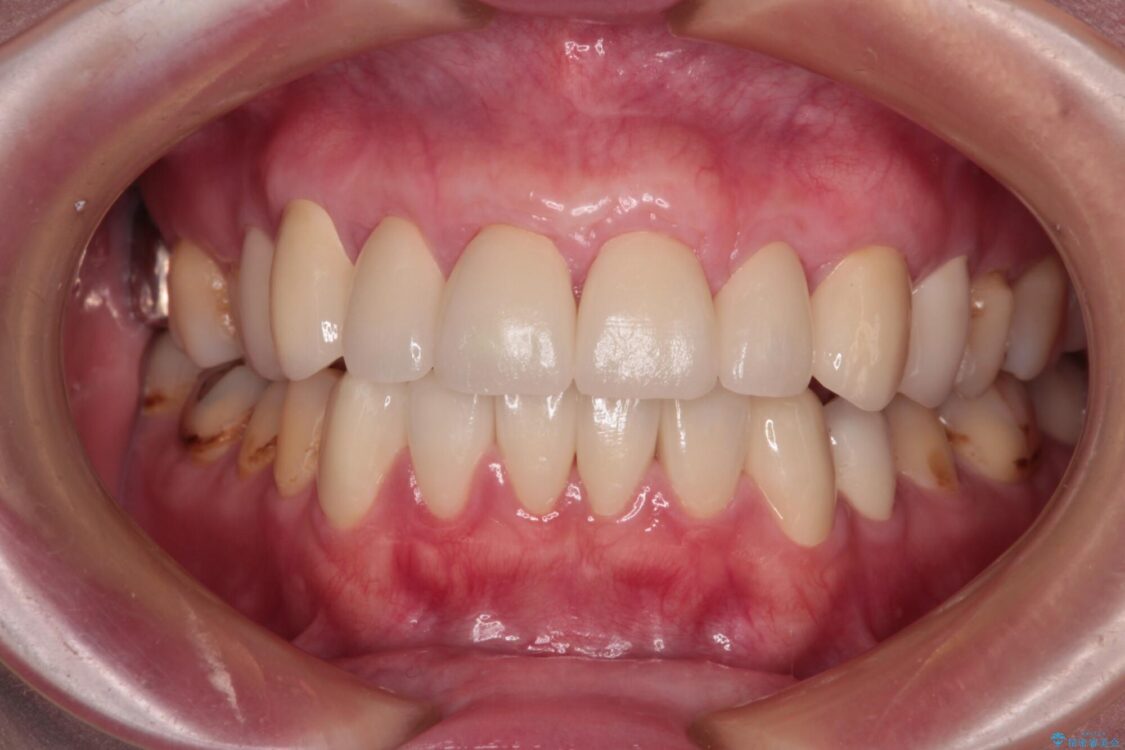

治療後について

歯肉移植術による根面被覆を行うかどうかは非常に悩まれていましたが、歯肉が覆われたことで長く見えていた歯の長さが整い、きれいな前歯の仕上がりとなりました。

治療後

• むし歯だらけの前歯をオールセラミッククラウンできれいに 治療後画像